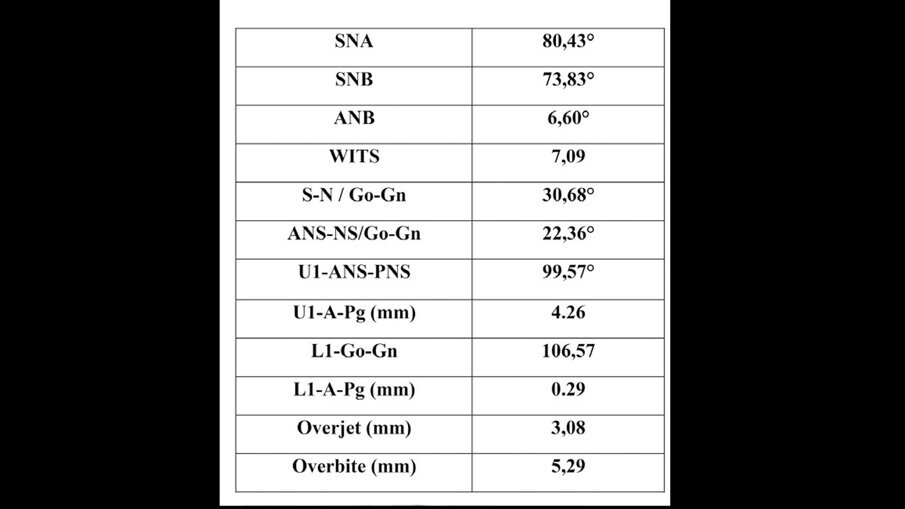

La paziente M. P. di anni 42 giunge alla nostra osservazione con la richiesta di un trattamento ortodontico di tipo estetico, al fine di migliorare l’allineamento dentale e l’esposizione del sorriso. All’analisi del volto si evidenzia un viso di forma quadrata, simmetrico ed un profilo dritto. All’esame funzionale non si rilevano disfunzioni dell’ATM. L’analisi cefalometrica (Figg. 3a-3c) evidenza una seconda classe scheletrica associata a ipodivergenza. Gli incisivi superiori presentano un’inclinazione rispetto al piano bispinale di 99,57° e la loro posizione rispetto alla linea A-Pg risulta nella norma. Gli incisivi inferiori (106,57°) sono protrusi rispetto al piano mandibolare e la loro posizione rispetto alla linea A-Pg risulta nella norma.

Figg. 3a-3c_Acquisizione dei records radiografici. Tracciato cefalometrico iniziale.

Figg. 3a-3c_Acquisizione dei records radiografici. Tracciato cefalometrico iniziale.

Figg. 3a-3c_Acquisizione dei records radiografici. Tracciato cefalometrico iniziale.

L’esame intraorale (Figg. 4a-4h) mostra un affollamento moderato in arcata superiore e inferiore e un morso profondo con un overbite di 5,29 mm, un rapporto inter-arcata di Classe II Suddivisione che si esprime con una Classe II testa a testa, sia molare sia canina a sinistra e una lieve Classe II canina e molare a destra. A complicare il quadro clinico le linee mediane non sono coincidenti, la superiore risulta deviata leggermente a destra. L’esame ortopantomografico mostra pregresse cure dentarie senza nessuna anomalia da segnalare. I valori cefalometrici dimostrano una tipologia brachifacciale con una sinfisi molto svirgolata, il che contrasta con un’eccessiva proclinazione anteriore degli incisivi.